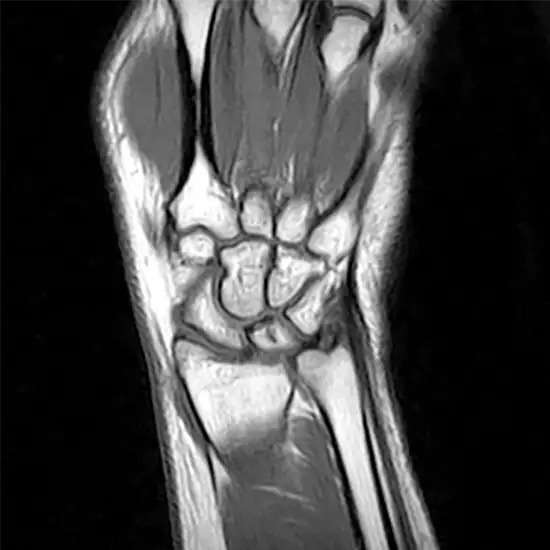

An MRI of the left wrist joint is used to visualize the bones of the wrist joint and the soft tissues around it, such as tendons, ligaments, muscles, and blood vessels. The wrist joint comprises the ends of the forearm bones and eight small bones called carpal bones (radius and ulna).

MRI (Magnetic Resonance Imaging) screening of the left wrist is a non-invasive medical diagnostic tool used to obtain detailed images of the left wrist and the related tissue in the left wrist. MRI Screening of the left wrist is used to show abnormalities like fractures, injuries, and strains of the left wrist.